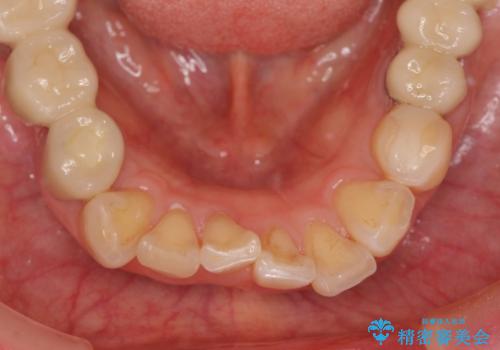

前歯の突き上げを改善する インビザライン による小矯正

- 下顎前歯のガタつきにより上顎前歯のクラウンに突き上げ・動揺が認められ、また歯ぎしりもあることから下顎前歯のみの小矯正をインビザライン で行うこととなりました。

下顎前歯の突き上げについて

噛み合わせが強くまた下顎に前歯にもガタつきが認められる場合、歯ぎしりやくいしばることで上顎前歯に大きな力がかかり歯の破折やクラウン損傷の大きなリスクとなることがあります。